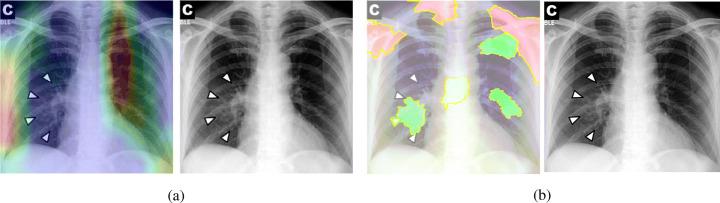

One of the primary clinical observations for screening the novel coronavirus is capturing a chest x-ray image. In most patients, a chest x-ray contains abnormalities, such as consolidation, resulting from COVID-19 viral pneumonia. In this study, research is conducted on efficiently detecting imaging features of this type of pneumonia using deep convolutional neural networks in a large dataset. It is demonstrated that simple models, alongside the majority of pretrained networks in the literature, focus on irrelevant features for decision-making. In this paper, numerous chest x-ray images from several sources are collected, and one of the largest publicly accessible datasets is prepared. Finally, using the transfer learning paradigm, the well-known CheXNet model is utilized to develop COVID-CXNet. This powerful model is capable of detecting the novel coronavirus pneumonia based on relevant and meaningful features with precise localization. COVID-CXNet is a step towards a fully automated and robust COVID-19 detection system.

筛查新型冠状病毒的主要临床观察方法之一是拍摄胸部X光图像。在大多数患者中,胸部X光显示出由COVID-19病毒性肺炎引起的异常,如实变。在本研究中,我们利用深度卷积神经网络在一个大型数据集中对这种类型肺炎的成像特征进行高效检测。结果表明,简单模型以及文献中的大多数预训练网络都关注于与决策无关的特征。本文收集了来自多个来源的大量胸部X光图像,并准备了一个最大的公开可用数据集。最后,使用迁移学习范式,利用著名的CheXNet模型开发了COVID-CXNet。这个强大的模型能够基于相关且有意义的特征精确地定位检测新型冠状病毒肺炎。COVID-CXNet朝着全自动且强大的COVID-19检测系统迈出了一步。